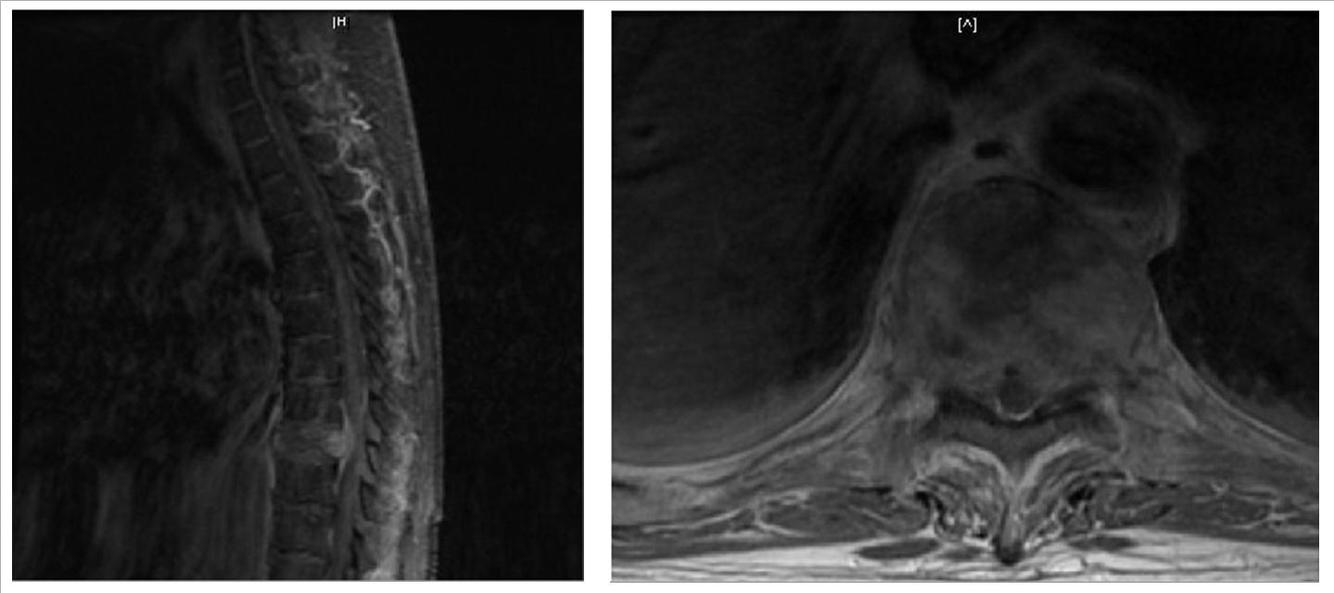

Apakah diagnosis yg plg mgkn terlihat pada MRI?

A. Invaginasi basilar

B. Chiari 1 malformasi

C. Pilocytic astrocytoma

D. Multiple sclerosis

E. Chordoma

The correct answer is Chiari 1 malformation.

There is cerebellar tonsillar ectopia (approximately 1 cm below the foramen magnum) with an associated cervical syrinx, findings consistent with Chiari 1 malformation. The contents of the syrinx correspond to CSF (i.e. T1 hypointense and T2 hyperintense). The lesion has distinct margins and displaces rather than infilatrates adjacent spinal cord.

Astrocytomas are infiltrating tumors. Basilar invagination refers to narrowing of the foramen magnum due to upward migration of the top of the C2 vertebrae. Multiple sclerosis causes demyelinating lesions of the brain and spinal cord and is not associated with tonsillar ectopia. Chordomas are primary bone tumors of notochord remnants that are extradural in location.